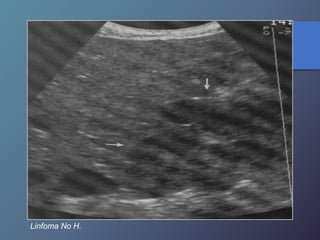

Linfoma No H.

Linfoma No Hodgkin en sida